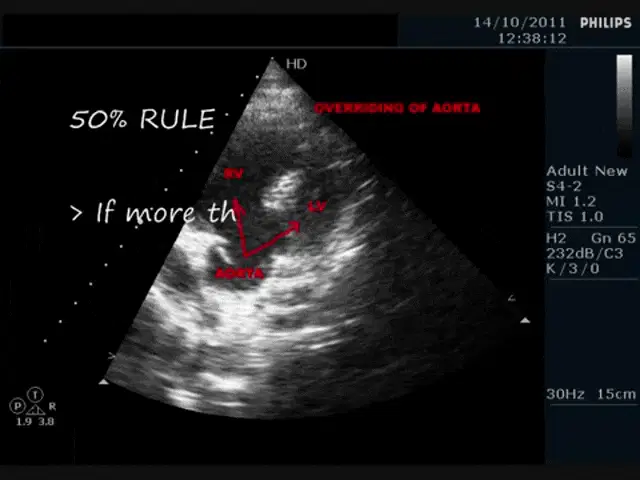

loadingTetralogy of Fallot Echocardiography